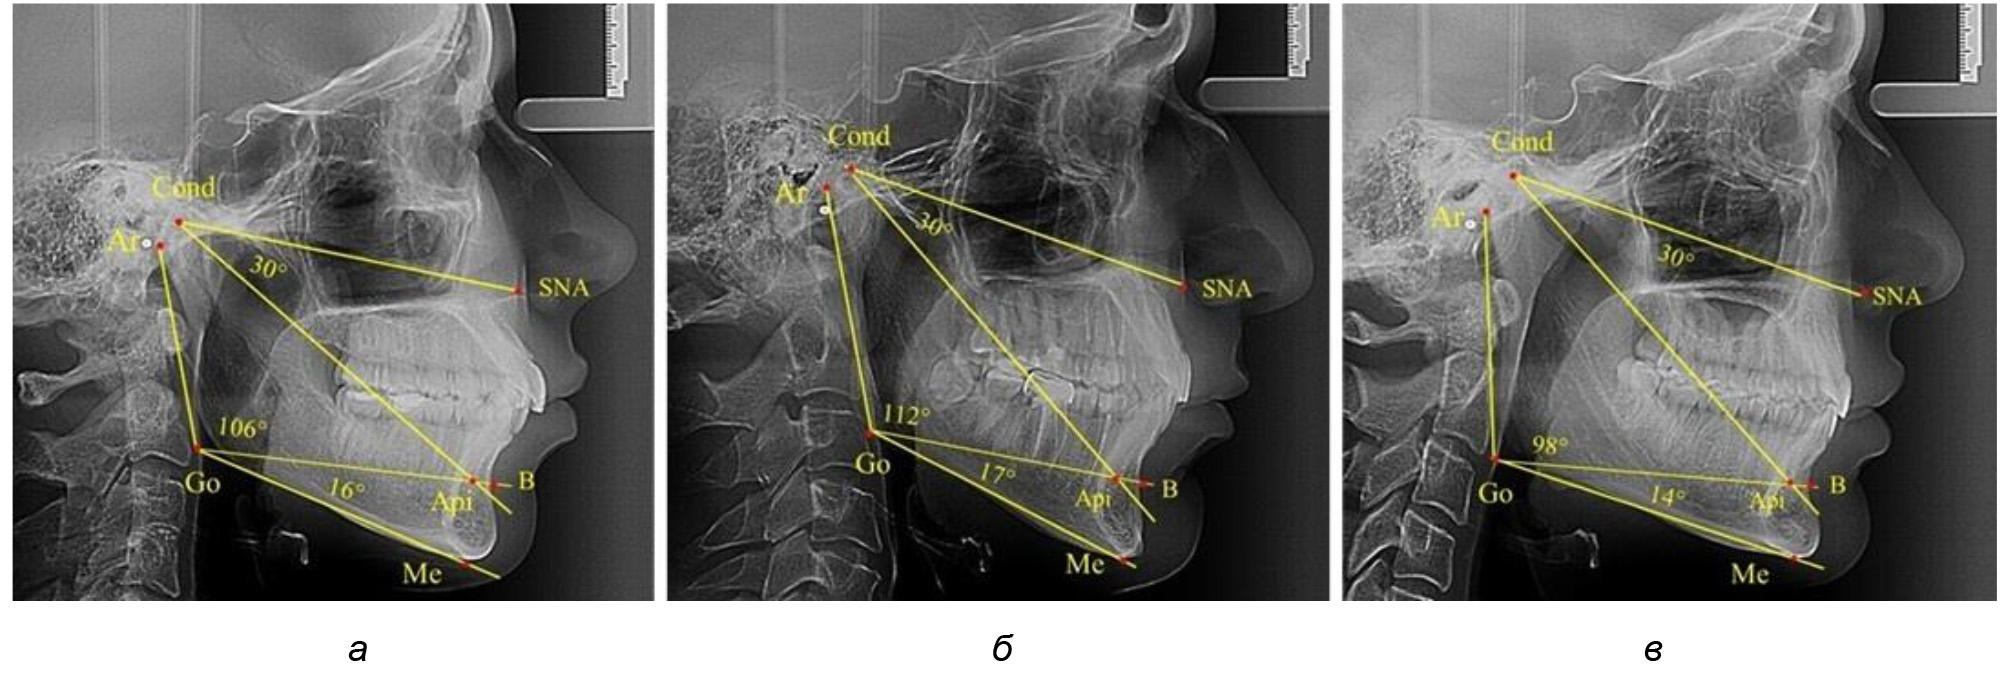

В то же время нижнечелюстной угол варьировал в широких пределах, в частности от 112 до 127°, и его средние значения при физиологическом прикусе составляли (120,57 ± 1,43)°. При этом составляющие части нижнечелюстного угла имели различия. Так, показатель угла Ar-Go-Api варьировал от 110 до 117°, при средних значениях – (107,12 ± 1,73)°. Величина угла Api-Go-Me составляла в среднем (13,56 ± 1,09)° при минимальных значениях 6° и максимальном показатели 19°. Анализируя параметры нижнечелюстного угла на телерентгенограммах с различными типами нижнечелюстного угла, выявлено, что у людей с нейтральными типами угла (в пределах от 119 до 123°) средний показатель был (121,83 ± 0,62)°. Величина угла Ar-Go-Api составила (107,89 ± 1,62)°, а угол Api-Go-Me был (13,83 ± 1,12)°.

При вертикальном типе нижнечелюстного угла его средние значения составили (125,51 ± 0,44)°, и достоверно отличалась от показателей людей с нейтральными значениями нижнечелюстного угла. Величина угла Ar-Go-Api составила (115,49 ± 2,14)°, а угол Api-Go-Me был (13,97 ± 1,26)°.

Для горизонтального типа роста было характерно достоверное р ˂ 0,05 уменьшение нижнечелюстного угла до (115,57 ± 0,56)°. Величина угла Ar-Go-Api составила (102,71 ± 1,62)°, а угол Api-Go-Me был (12,86 ± 0,74)° (рис. 3).

Рис. 3. Особенности ТРГ при нейтральном (а), вертикальном (б) и горизонтальном (в) типе угла нижней челюсти в постоянном прикусе

Таким образом, вне зависимости от величины нижнечелюстного угла, показатели угла гнатической части лица были в пределах 30°, что может расцениваться в качестве оптимального физиологического показателя параметров гнатической части лица. Анализ ТРГ проведен у 31 ребенка в различные периоды дентального онтогненеза, включая прикус молочных зубов и различные группы прорезывания постоянных зубов.